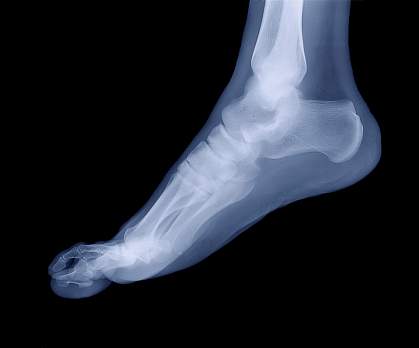

Nearly 3 million adults in the United States are estimated to have gout. Gout can develop when excess amounts of uric acid build up in the blood and form crystals. These crystals accumulate in joints to cause swelling and pain. Gout often first affects the joints of the big toe, but many other joints can also be affected. Left untreated over time, gout can permanently damage affected joints.